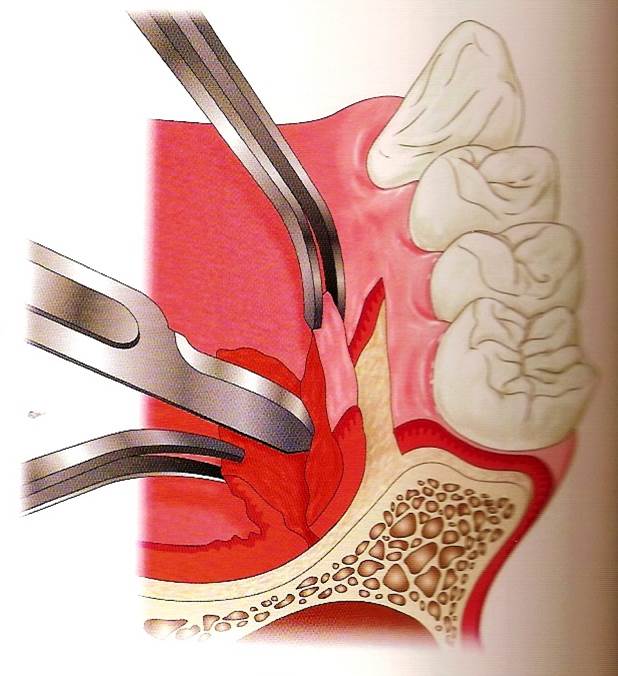

自體骨移植術是患者本身要植牙的位置缺少骨頭,用病患自己身上的骨頭或骨屑,移植到要植牙但缺少骨頭的區域。骨頭的來源不限於口腔內,尤其是缺很多骨頭時,像是口腔癌或是特殊的患者,骨頭的來源可能是肋骨或腿骨,平常較常見的是若骨頭缺損比較多的情況下,從下巴處或智齒後取得骨塊;如缺損比較少時,會利用做植牙手術在鑽骨頭時,收集鑽骨所產生的骨屑來補,簡單來說就是拿病人自己的骨頭來補缺損、不足的地方。病患不用擔心自體骨移植是否會產生排斥的現象,因為自體骨移植是取自於自己身上的骨頭,所以並不會產生排斥的現象,新種下去的骨頭或骨粉經重新生長過後與底下的骨頭結合。自體骨移植相對於植牙而言,不一定會比較便宜或比較貴,因為費用會因病人的狀況、手術施作的難度而有所影響,因為簡單的可能只是稍微的將骨頭刮一刮就可以補了,但也有可能是需要另外從身體別處取得較大量的骨頭,相對而言後者就困難許多,因此手術費用的高低會因為手術的困難程度而有所影響。(圖26-29)

圖26

圖27

圖28

圖29